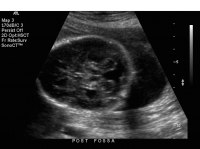

Dandy Walker Malformation and Variants

Dandy walker malformation